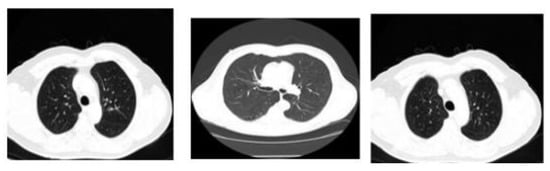

All the images used in this research are also accessible in the database, with the pivotal point of view. Here, the framework size is (256 × 256) or (512 × 512) and 16 bits for every pixel. Lung Image Database Consortium (LIDC) is where the JPEG format of lung images is available. For research purposes of radiologists, they can easily access that database through Cancer Imaging Archive (CIA) [29]. Some samples from the databases are shown in Figure 3. The proposed system data set consists of images of 290 patients, of which 250 patient datasets are used for training the classifier, and the remaining 40 patient datasets are used for validation. The data set obtained is of DICOM format and is converted to 512 × 512 by pre-processing method without data loss for further partitioning and refinement purposes. Table 1 summarizes the dataset used, and Table 2 shows the scanner difference.

Figure 3.

CT image of lungs from the dataset: LIDC in the different sagittal planes.